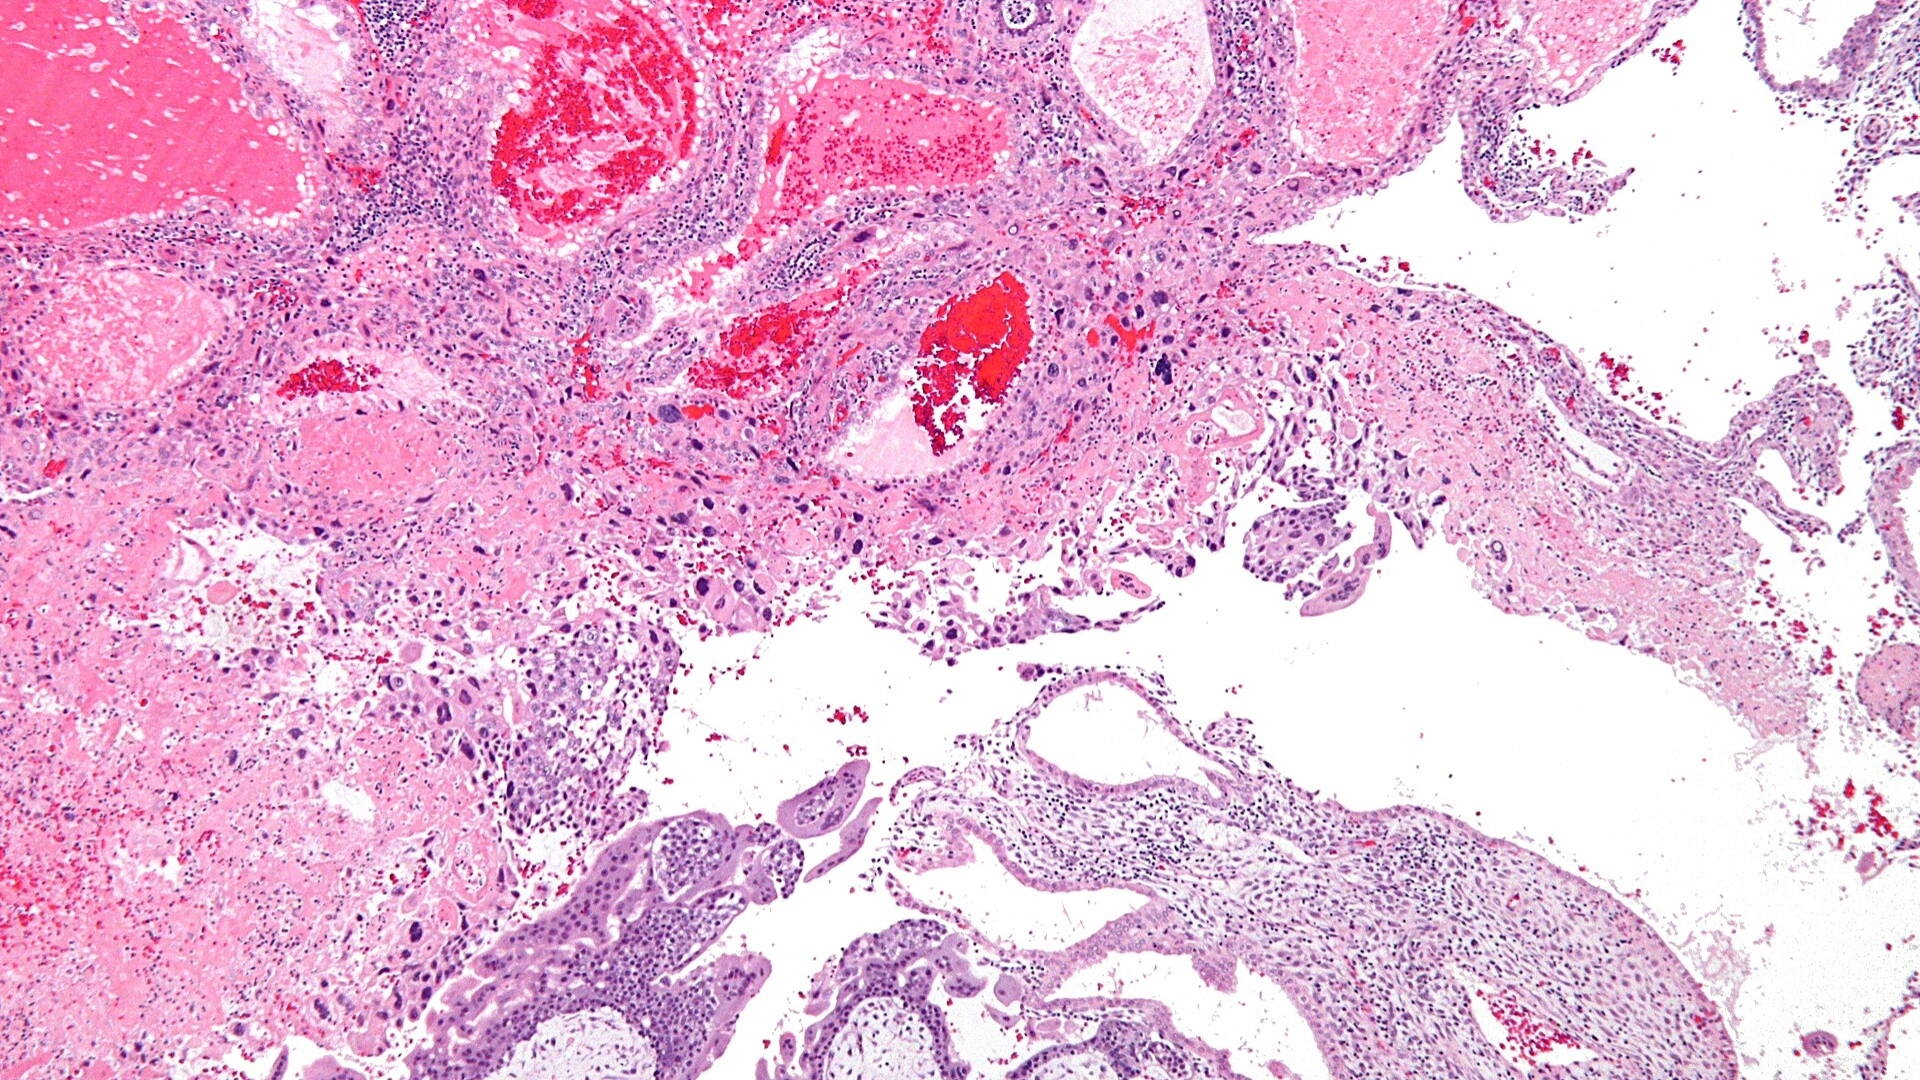

Gestational Trophoblastic Disease (GTD) describes a rare group of tumors originating from placental tissue, specifically from cells known as trophoblasts. Trophoblast cells typically develop into the placenta during pregnancy, helping nourish the embryo. However, abnormalities in trophoblast cells can lead to uncontrolled growth, forming tumors or cysts, and initiating Gestational Trophoblastic Disease (GTD).

While specific hereditary genes linked distinctly to GTD are rare, genomic studies highlight chromosomal abnormalities relating to GTD subtypes. For example, complete hydatidiform moles frequently result from duplication of paternal genome (46XX karyotype, entirely paternal origin). Conversely, partial hydatidiform moles typically display triploid karyotypes (69 chromosomes), blending both maternal and paternal material.

Notably, GTD cells’ unusual dependence on glucose uptake represents a prime metabolic vulnerability for targeted therapies. Demonstrating features akin to the Warburg effect, these trophoblastic cells preferentially consume glucose rapidly and abundantly, expediting growth and facilitating malignant progression.

• Overexpression of glucose transporters (GLUT1) enabling accelerated glucose uptake.

• Amplified glycolytic activities ensuring rapid cellular growth.